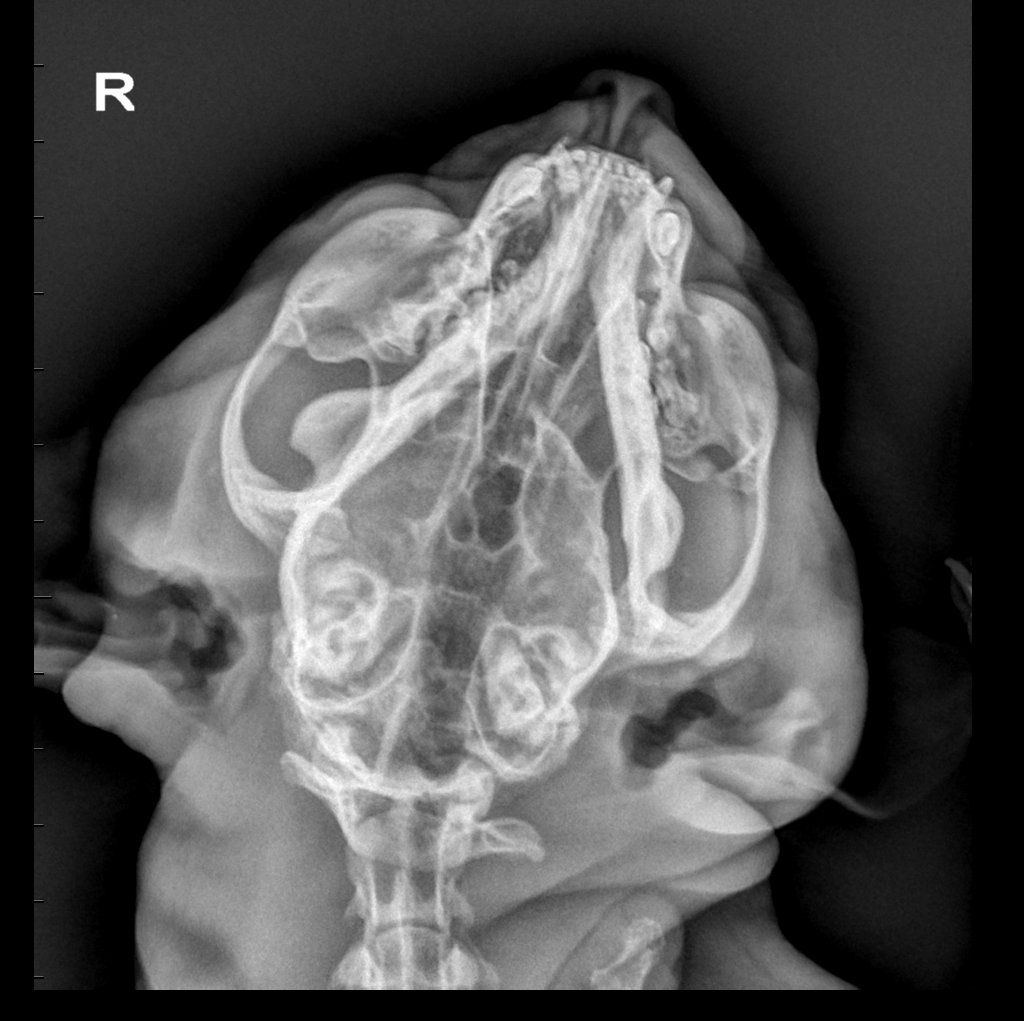

Diagnostica per immagini

Tra i servizi che l’Ospedale Veterinario Città di Conegliano fornisce, non mancano quelli di diagnostica per immagini:

ecografia, radiologia digitale, TC.

Gli specialisti Roberto De Pellegrin e Riccardo Pelizzon, in particolare, si occupano degli esami ecografici, ecocardiografici, tomografici per l'acquisizione di immagini del corpo del paziente attraverso l'esposizione a ultrasuoni o a raggi X.

Si tratta di esami non invasivi né dolorosi, che possono essere eseguiti molto rapidamente.